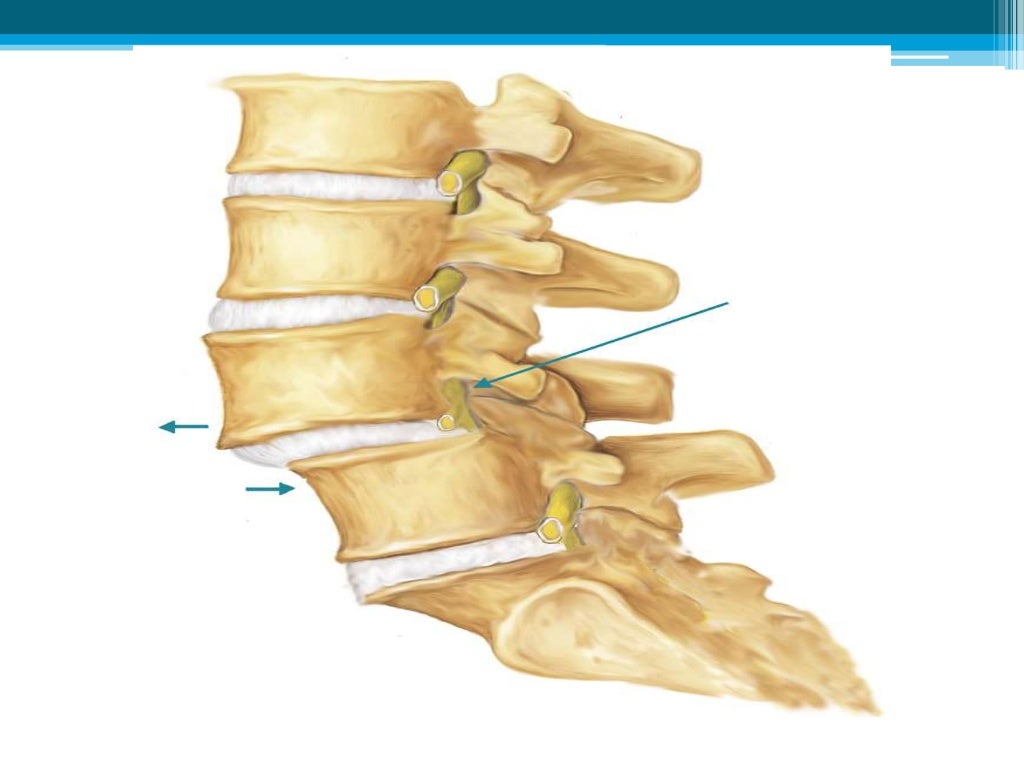

Qué Tan Grave Es La Espondiloartrosis, ¿Qué es la espondiloartrosis y cuál es su tratamiento, 11.47 MB, 08:21, 384,827, FisioOnline, 2016-09-04T10:29:46.000000Z, 3, Pin en articulaciones / huesos, www.pinterest.com.mx, 1280 x 720, jpeg, WebLa espondiloartrosis puede ser potencialmente grave y puede limitar la movilidad de la columna. Los síntomas pueden variar desde un dolor leve hasta un dolor intenso.. WebLa espondiloartrosis o artrosis de la columna vertebral es una enfermedad degenerativa de los cartílagos de las articulaciones que puede afectar a la zona. WebLa espondiloartrosis es un tipo de artrosis que afecta a la columna vertebral, en la que las vértebras, los discos y el cartílago se deterioran. Al deteriorarse el cartílago, las., 20, que-tan-grave-es-la-espondiloartrosis, Novedades y Muebles WebLa espondiloartrosis puede ser potencialmente grave y puede limitar la movilidad de la columna. Los síntomas pueden variar desde un dolor leve hasta un dolor intenso.. WebLa espondiloartrosis o artrosis de la columna vertebral es una enfermedad degenerativa de los cartílagos de las articulaciones que puede afectar a la zona. WebLa espondiloartrosis es un tipo de artrosis que afecta a la columna vertebral, en la que las vértebras, los discos y el cartílago se deterioran. Al deteriorarse el cartílago, las.

WebLa espondiloartrosis lumbar es la artrosis en la columna, que produce síntomas como dolor intenso en la espalda, causada normalmente por el desgaste de la articulación. No en. WebSi la espondilosis cervical comprime gravemente la médula espinal o las raíces nerviosas, el daño puede ser permanente. Hay un problema con la. WebLa espondiloartrosis es un cambio relacionado con la edad de los huesos (vértebras) y discos de la columna vertebral. Estos cambios a menudo se llaman enfermedad. WebLa espondiloartritis es grave. Pero con las estrategias de adaptación adecuadas y un plan de tratamiento coherente, la mayoría de las personas con la afección viven una vida plena. WebLa Espondiloartrosis o también Artrosis de Columna vertebral es una enfermedad degenerativa que afecta a los cartílagos de las articulaciones, provocando diversas. WebLa espondiloartrosis es una enfermedad degenerativa de la columna vertebral, que puede ser prevenida si se realza lo necesario en el momento indicado Es por esto, que aquí en. WebEl objetivo del tratamiento es aliviar el dolor y la rigidez, y prevenir o retrasar las complicaciones y la deformidad de la columna vertebral. El tratamiento de la espondilitis anquilosante es más exitoso antes de que la enfermedad cause daño irreversible. WebLa espondiloartrosis o artrosis (1) de la columna vertebral, es una patología degenerativa que causa desgaste del cartílago articular de las articulaciones.

WebLa espondiloartrosis, también llamada artrosis lumbar, es una degeneración de los cartílagos de la columna lumbar que genera dolor, rigidez y limitación del movimiento. WebLa espondiloartrosis lumbar se clasifica en cuatro grados, según la cantidad de daño que se haya producido en la columna vertebral. El grado I es el menos grave, y el grado IV es el. WebLa espondiloartrosis es una enfermedad degenerativa de las articulaciones que no presenta clínica hasta que los nervios está afectados y tampoco tiene cura. La.